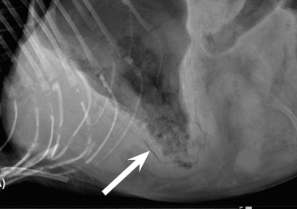

췌장염이 심한 고양이는 다양한 증상이 있을 수 있으나 그중에서 특이하기도 하고 드물게 발생한는 기종성 위염에 관한 논문이 나왔다.

논문이라기 보다는 이런 신기한 친구들도 있다는것을 알려주는 증례이니 참고만 할것.